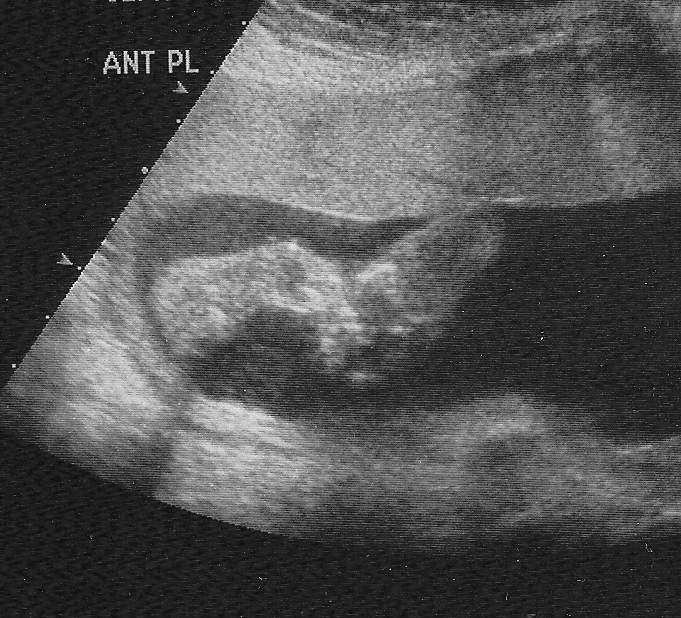

what does a boy look like on ultrasound

Normal 24 week baby ultrasound, the useful guide.

Normal 17 week baby Ultrasound. – Ultrasoundfeminsider

Ultrasound Images Of Baby Boy At 27 Weeks – Baby Viewer

32 week ultrasound for growth – Glow Community

Karnes Family Blog: Ultrasound pictures of Baby Boy Karnes!

Ornstein Boys’ Blog: A few pictures of MNO at the level 2 ultrasound on …